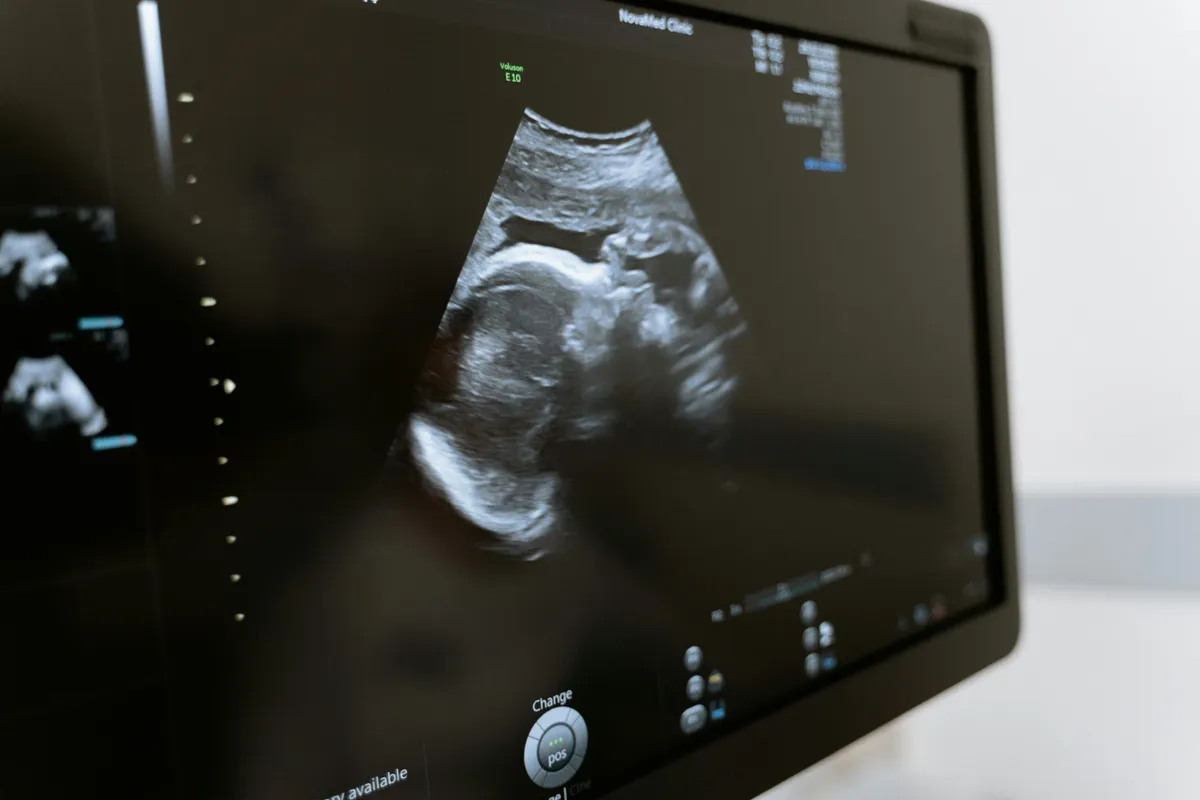

A kezelések azonban hatással voltak a termékenységére, és az orvosok azt mondták neki, hogy természetes úton szinte biztosan nem eshet teherbe. Ennek ellenére idén májusban kiderült: kisbabát vár.

Frankie-Ella ma már 35 hetes kismama, aki január elejére várja a kislányát.

Frankie-Ella a kezelések alatt több mint 28 gerincbe adott beavatkozáson esett át, ami miatt most kiemelten magas kockázatú kismamának számít. Hetente kétszer végeznek a vizsgálatokat, és külön szülési tervet készítenek a számára - írja a Mirror.